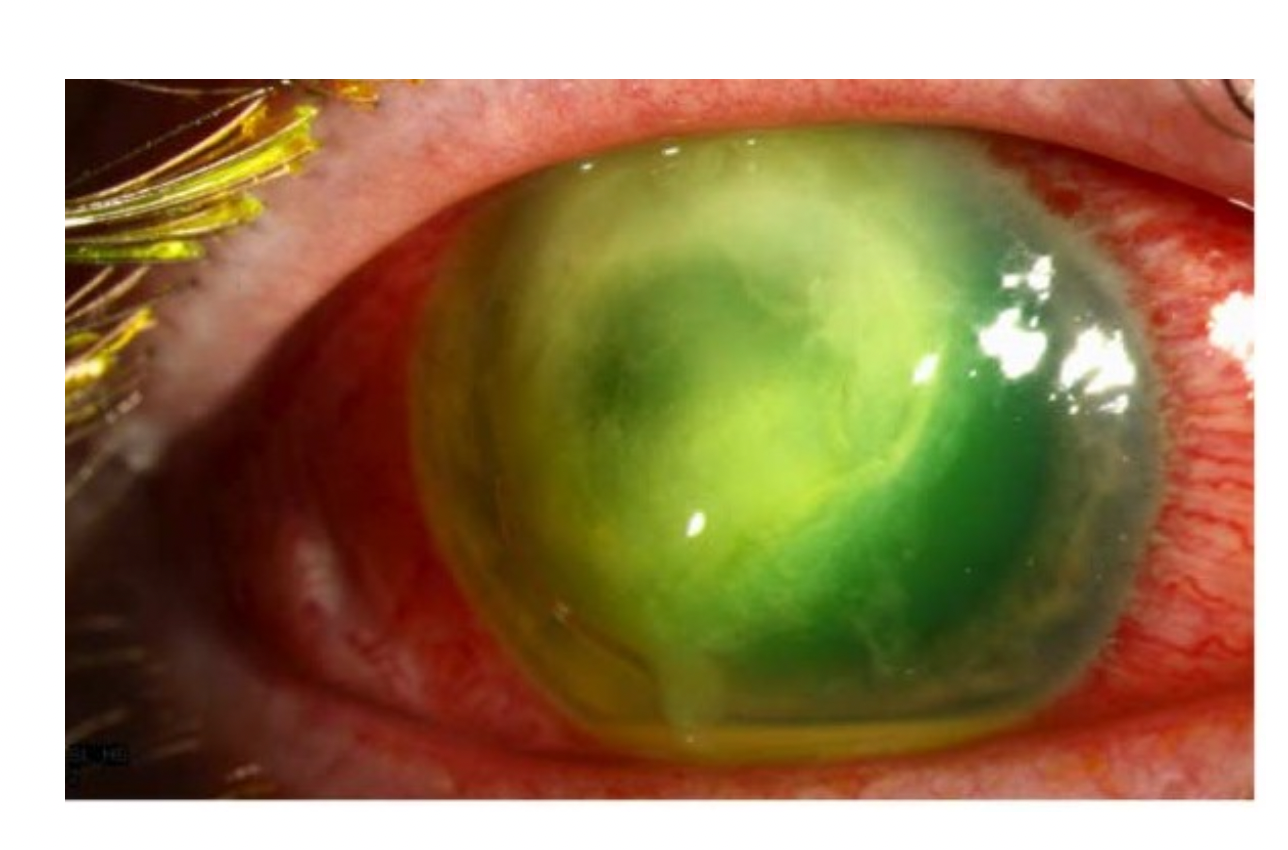

Bulbus: højre øje (se foto), normale forhold venstre øje

Hvad er mest sandsynlige diagnose?

- Fremmedlegeme på cornea

- Abrasio cornea

- Anterior uveit

- Keratit

- Akut glaukom

- Anterior uveit

Hvis øjet i stedet for havde set sådan ud, hvad skulle øjenlægen så have behandlet øjet med?

Svar:

1. Bredspektrede antibiotiske øjendråber

2. Antiviral (fx aciclovir) øjensalve 5 gange dagligt

3. Systemisk steroid

4. NSAID dråber (fx voltaren) 4 gange dagligt

5. Steroid øjendråber (fx dexamethason) 3 gange dagligt

- Antiviral (fx aciclovir) øjensalve 5 gange dagligt

Note:

Billedet viser en viral keratit.

Det behandles med antiviralke midler i form af aciclovir 5 gange dagligt i 14 dage.